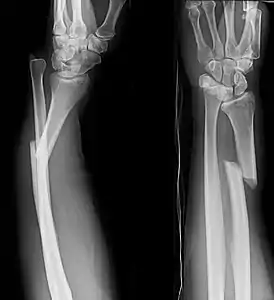

Изображения

Кости предплечья, вид спереди

Кости предплечья, вид сзади